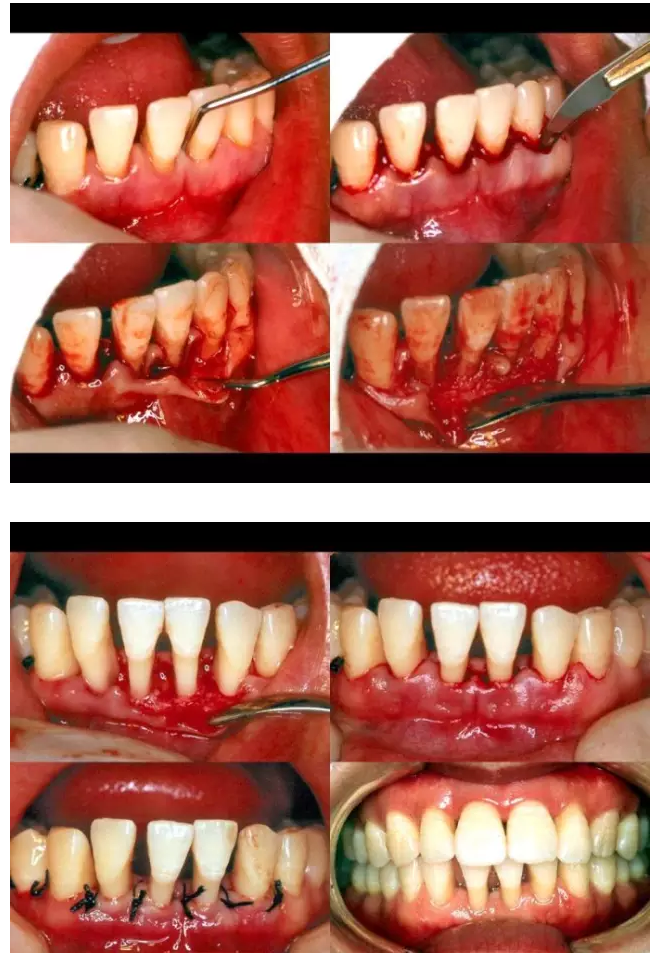

相關(guān)牙周防治